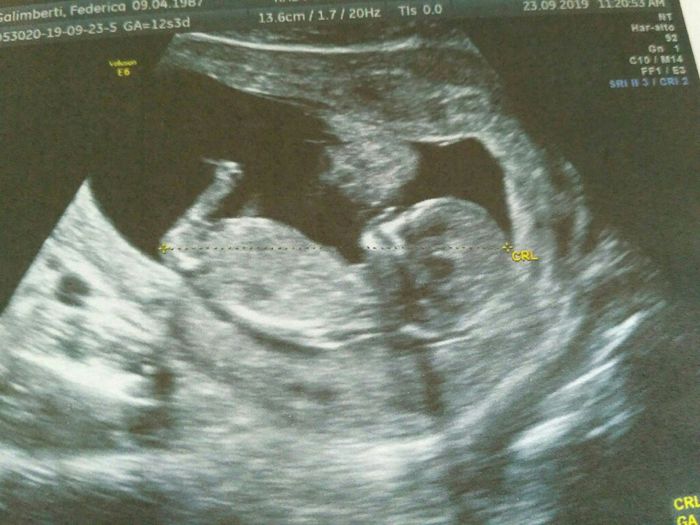

Mi affido a voi esperte di Nub Theory, cosa dite maschio o femmina??